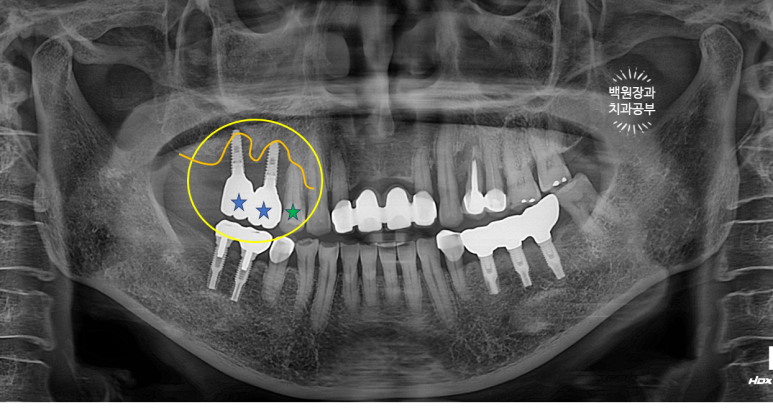

오른쪽 위 임플란트 2개를 약 10년 전에 수술하신 분입니다.

노란색으로 동그라미 쳐져 있는 부위의 임플란트 주변 잇몸에서 고름이 나온다고 하셨어요.

이미 잇몸뼈는 주황색 선처럼 매우 많이 사라져 버린 상태..... 이미 임플란트 주변 뼈는 모두 사라져 빠지기 직전.

보시면 녹색 별로 표시한 자기치아도 주변 뼈가 이미 많이 없어진 것을 보실 수 있습니다.

임플란트 주위염이 심해지면 주변 자연치아도 못쓰게 됩니다. 정기검진을 꼭 다니셔야하는 이유입니다.